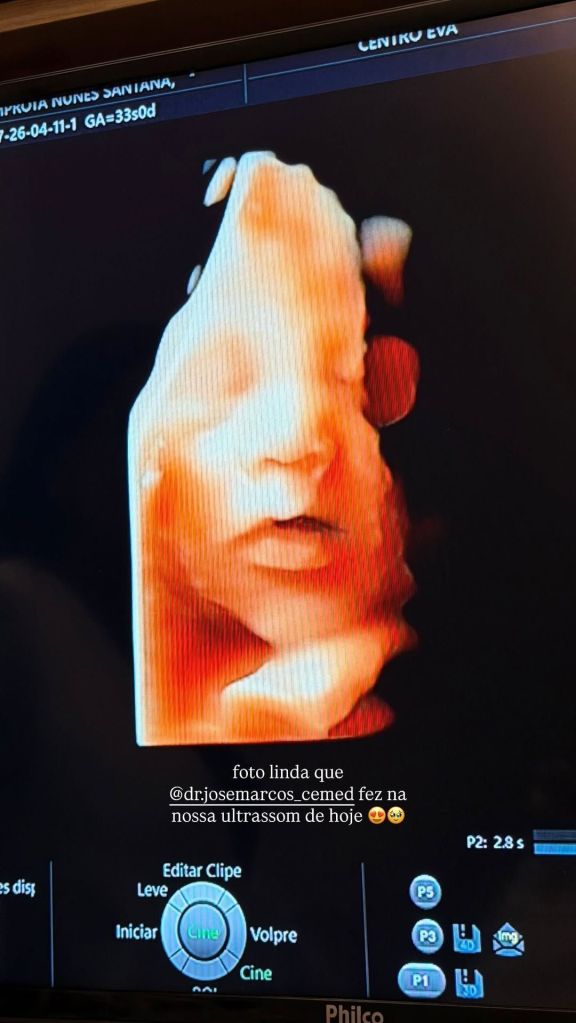

Já nas redes sociais, ela aproveitou para compartilhar as imagens do ultrassom de Levi, fruto do casamento com Léo Santana, 37.

No vídeo, ela aproveitou para comentar sobre os traços do bebe. “Nosso Levi está lindão e a cara de Liz e do papa Léo Santana. A mami não tem vez”, declarou na legenda da publicação.